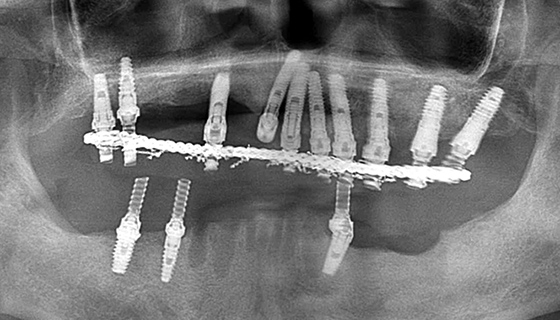

上顎前歯部を再インプラント

治療は終了し経過観察の時点で、上の前歯部のインプラントを繋げたブリッジが動揺しており、インプラントが抜けてきました。

インプラントを撤去した穴からは膿が出てきました。撤去したインプラント表面には骨はついておらず、プラークがべったり付着していました。

撤去したインプラントの隣にあるブローネマルクインプラントは、既に周囲の骨が溶けて無くなっており、ネジが露出していたため、その部分をしっかりと清掃し、骨補填材を入れました。また、抜けたインプラント部分には、2本のブローネマルクインプラントを埋入し、縫合したのち、仮歯を固定しました。

9ヶ月後

9ヶ月後に上顎の前歯に人工歯を装着しました。